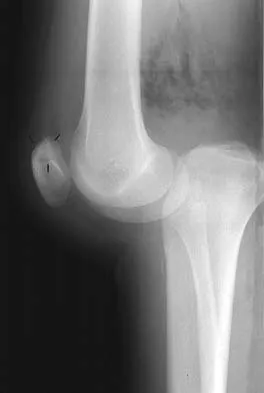

A 45-year-old male karate instructor sustained the injury shown in Figures 40a through 40c while practicing karate. The decision to proceed with surgery depends on which of the following factors?

The most important criteria in determining the need for surgery following a nondisplaced or minimally displaced tibial plateau fracture is knee stability to varus/valgus stress. Soft-tissue injury noted on MRI may be addressed at a later time following fracture healing. This fracture pattern is amenable to nonsurgical management. Decisions regarding surgical intervention may be made up to 2 weeks after injury.